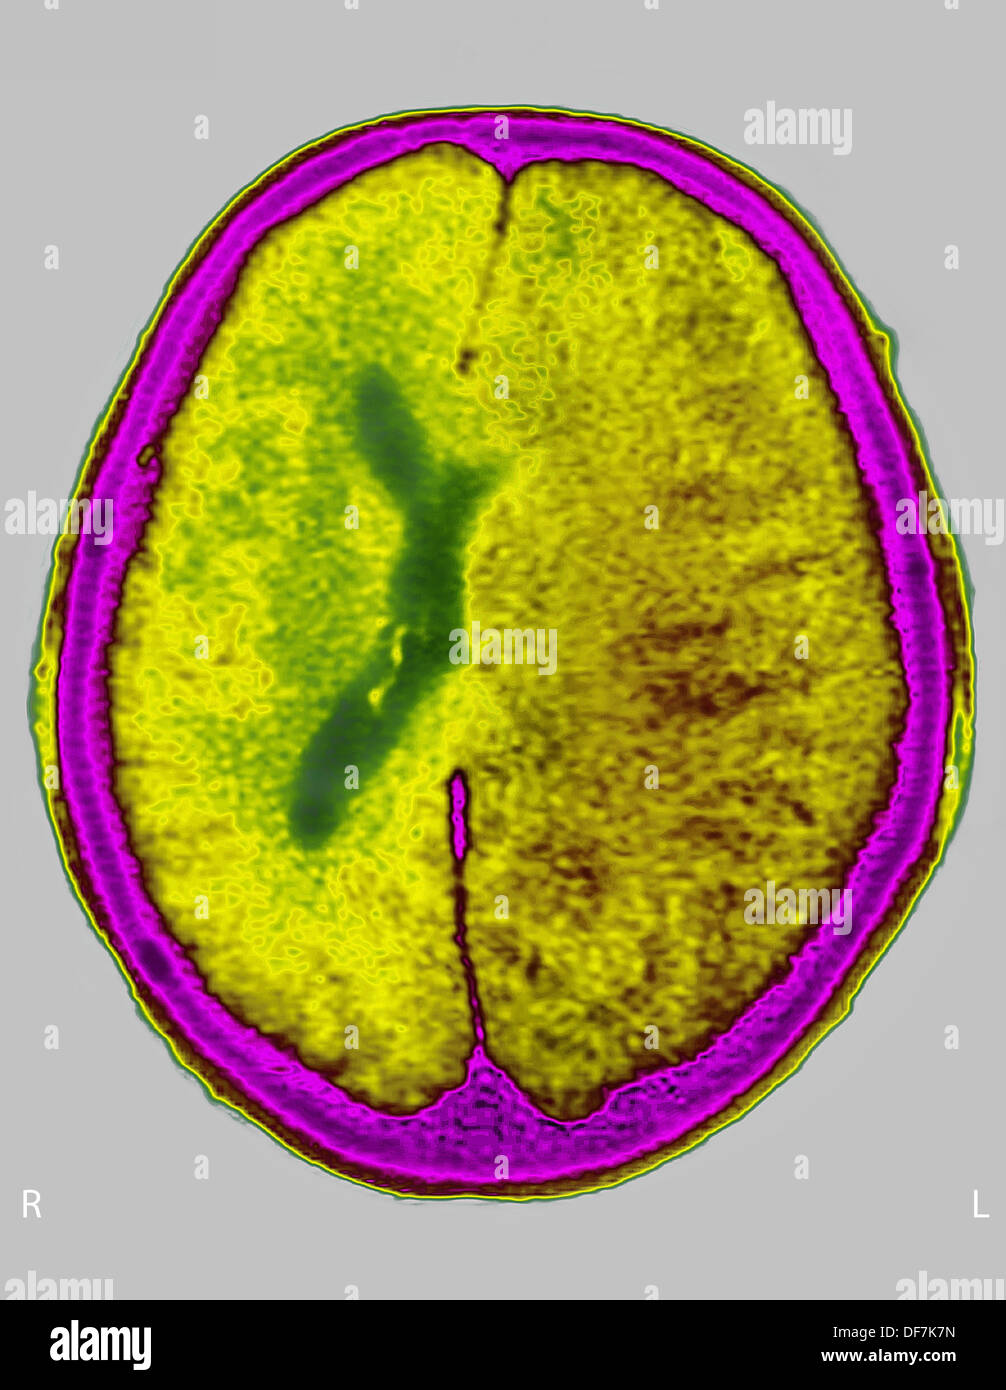

L'ŒDÈME CÉRÉBRAL CT SCAN Banque D'Imageshttps://www.alamyimages.fr/image-license-details/?v=1https://www.alamyimages.fr/l-oedeme-cerebral-ct-scan-image61019721.html

L'ŒDÈME CÉRÉBRAL CT SCAN Banque D'Imageshttps://www.alamyimages.fr/image-license-details/?v=1https://www.alamyimages.fr/l-oedeme-cerebral-ct-scan-image61019721.htmlRMDF7K7N–L'ŒDÈME CÉRÉBRAL CT SCAN